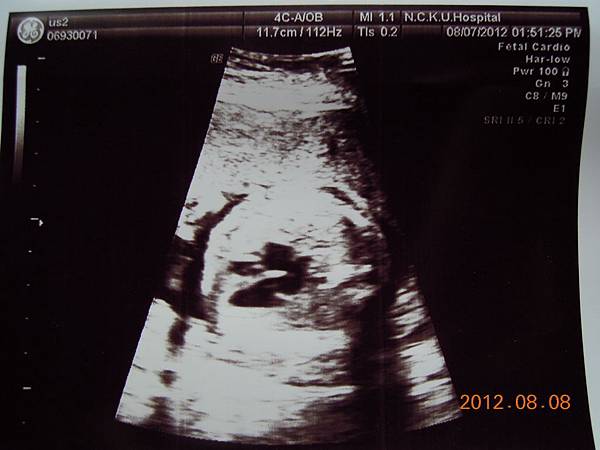

高層次超音波是用較精密儀器,並花較多時間仔細檢查胎兒的每一個部位和器官,所以還是把這兩千元花下去~

女醫師看起來超熟練,一邊照還會邊跟我解釋,這是逼逼的大腿,小腿,心臟,腎臟.....等等器官,一邊跟我媽聊天,說他生幾個....

除了比較明顯的骨頭可以看的出來,其實我們看不太懂,但是他精熟的技術很快把每個部位的大小都量測出來,我躺在床上看著上頭的螢幕,慢慢欣賞他的每張超音波照片~~

大約檢查了有四五十分鐘,也數了他的手指腳趾,看起來是沒異狀,就叫我等下把報告拿過去門診給游醫師看,還給我ㄧ堆照片,就是下面那些~~